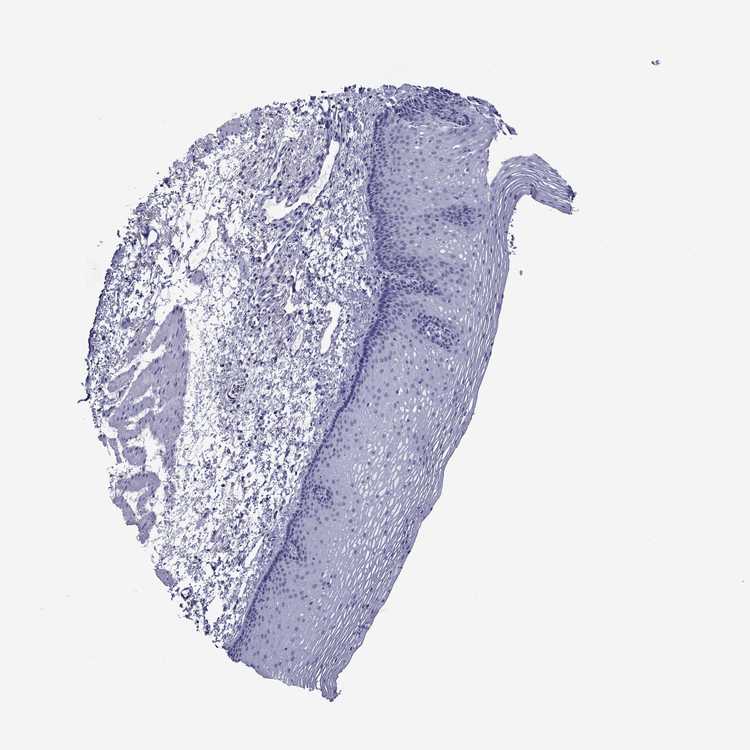

TISSUE PRIMARY DATA ESOPHAGUS Show tissue menu

Esophagus

ESOPHAGUS - Antibody stainingi

Antibody staining in the annotated cell types in the current human tissue is reported as not detected, low, medium, or high, based on conventional immunohistochemistry profiling in selected tissues. This score is based on the combination of the staining intensity and fraction of stained cells.

Each image is clickable and will lead to virtual microscopy that enables deeper exploration of all samples and also displays staining intensity scores, fraction scores and subcellular localization as well as patient and tissue information for each sample.

Antibody HPA055223Antibody HPA076419

Squamous epithelial cells MediumNot detected